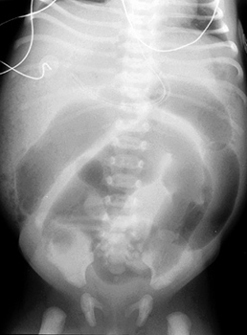

Pediatric Radiology > Abdominal > Neonatal > Meconium Ileus - Radiographic Features

Meconium Ileus - Radiographic Features

Microcolon (unused colon) · "Frothy" or "soap-bubble" pattern of bowel gas (air mixed with meconium), often in the right lower quadrant · Dilated small bowel loops · Small bowel obstruction · Calcification due to meconium peritonitis (15%) · Distal ileum packed with meconium and larger than microcolon on contrast enema |